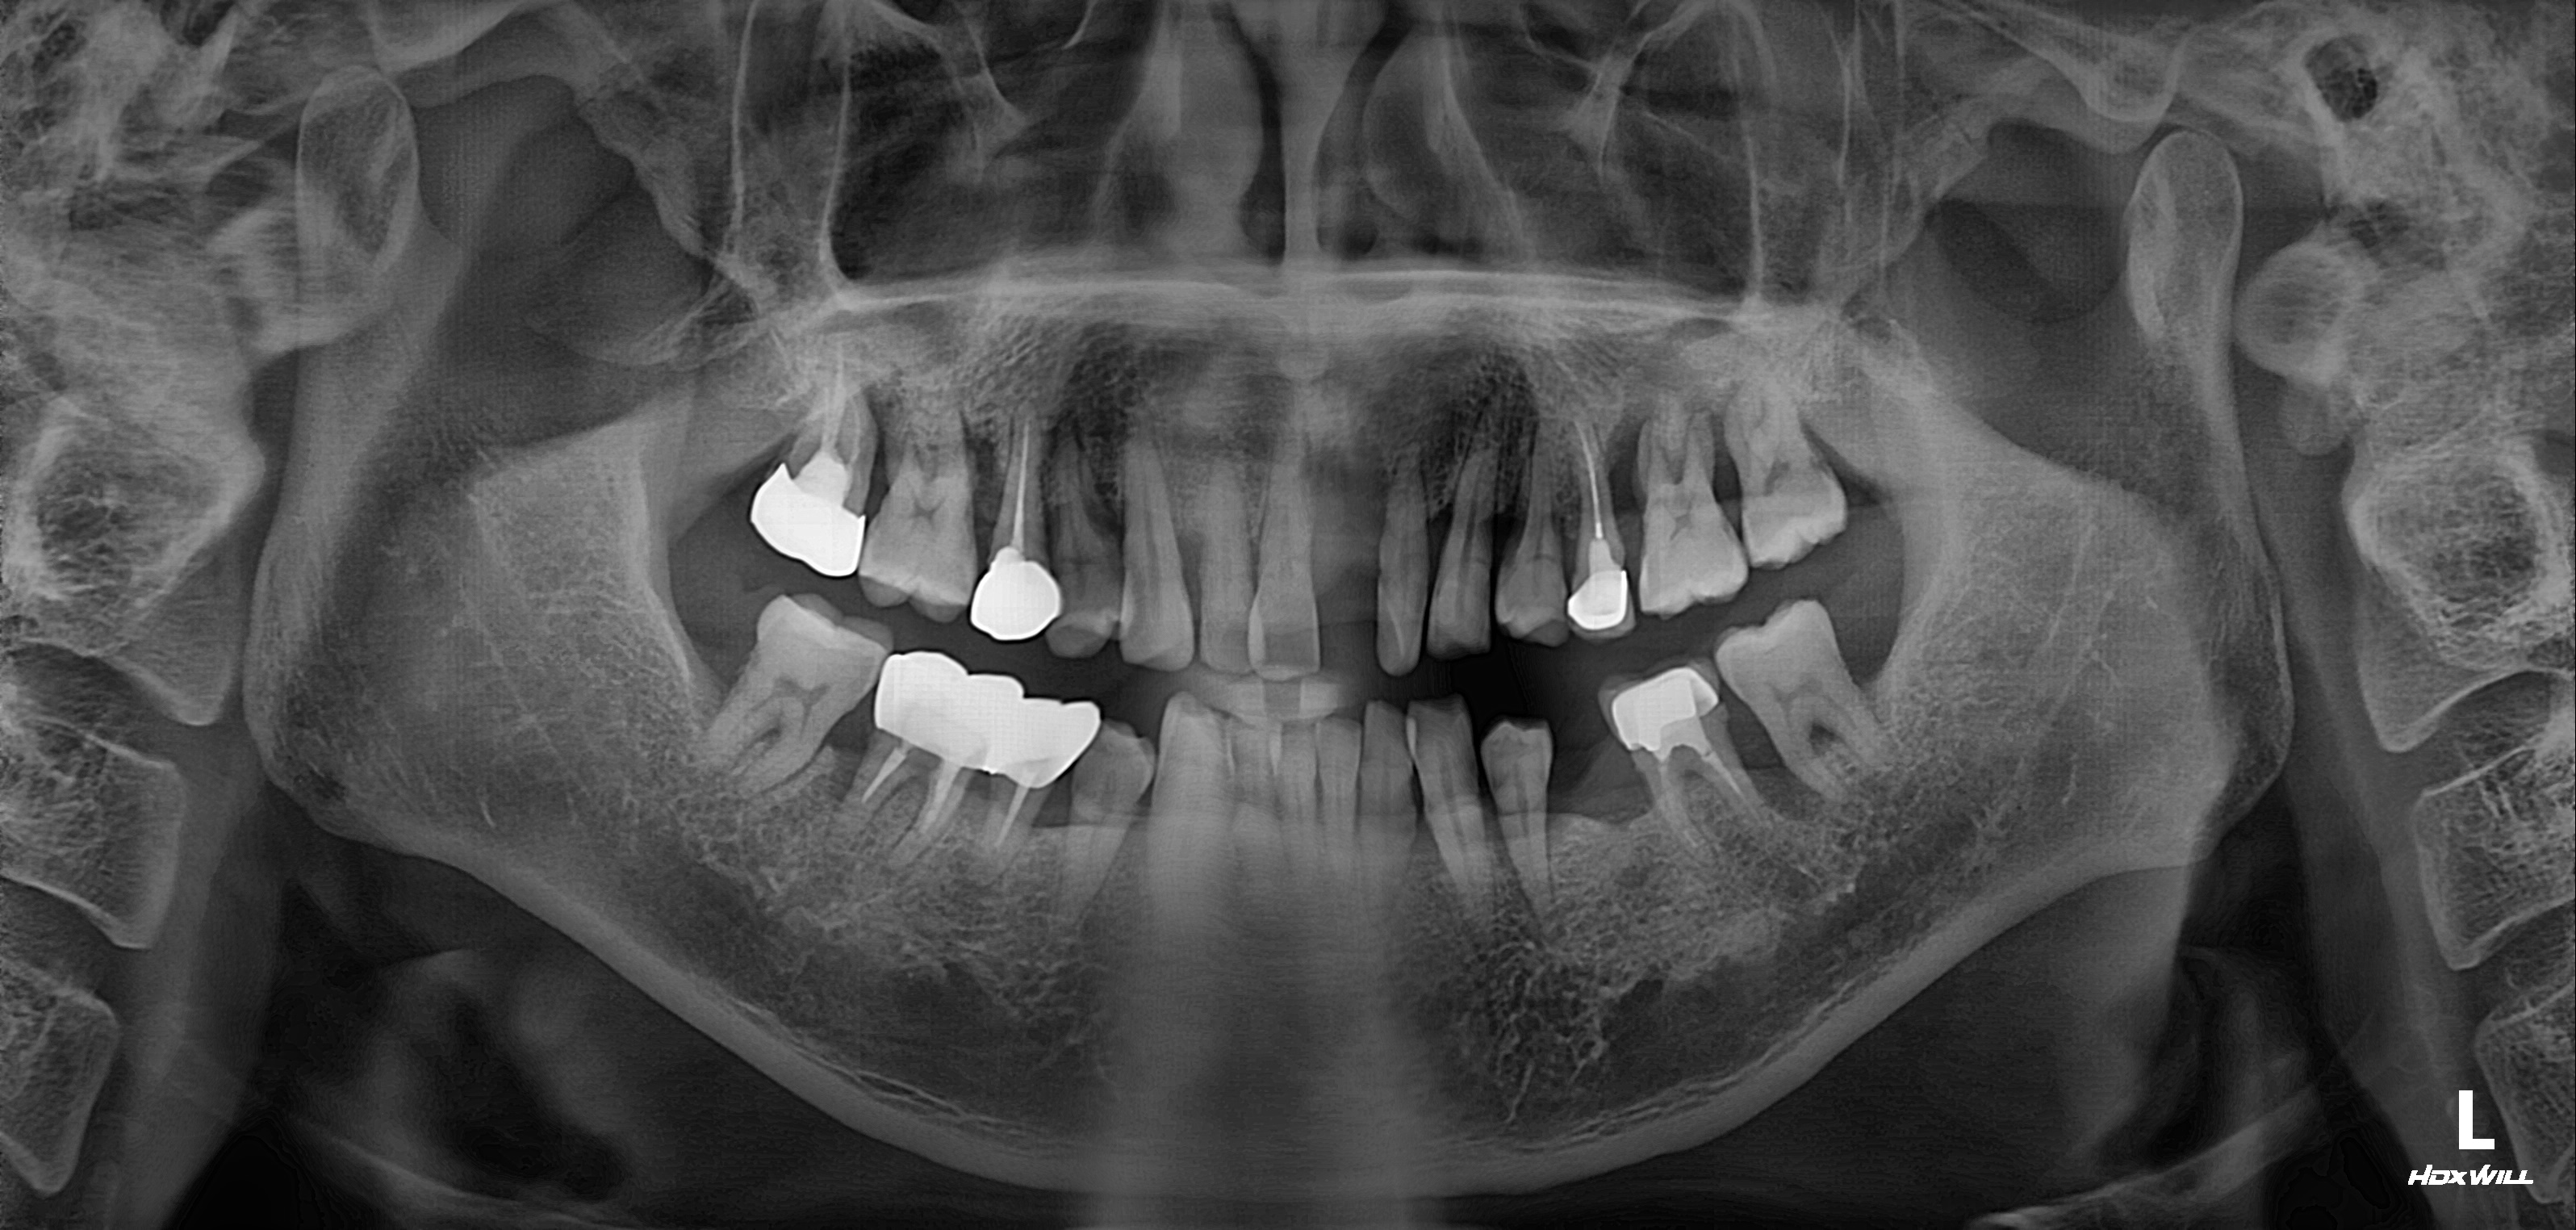

수술 전

수술 후

전악임플란트 식립사례

전후사진